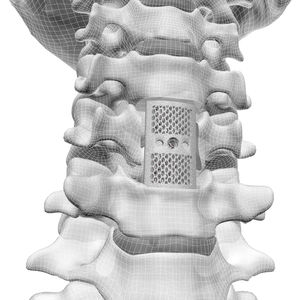

Prótesis para corpectomía vertebral

... La técnica de corpectomía XLIF permite a los cirujanos tratar a los pacientes con corpectomía mediante una exposición reproducible y mínimamente disruptiva que proporciona una visualización directa de la zona afectada. Una ...

... columna vertebral) se utiliza principalmente para los pacientes que requieren la reconstrucción de la estabilidad de la columna vertebral debido a la fractura de la columna vertebral, la enfermedad degenerativa, ...

... Fortalecer el anillo final para prevenir el colapso postoperatorio del cuerpo vertebral.

... - Material de aleación de titanio - Superficies superior e inferior dentadas para un agarre máximo - Diseño eficiente que proporciona un amplio espacio de injerto - Mecanismo de bloqueo de una etapa para evitar el desplazamiento - Implantación sencilla ...

... • Permitir un contacto completo con la superficie vertebral • Proporcionar una fijación segura con la característica de superficie roscada • Espacio de injerto eficiente antes de la distracción • Proporcionar un mecanismo de bloqueo ...

... La jaula de corpectomía CC3 es un reemplazo de cuerpo vertebral para la estabilización de la columna throcalumbar. La jaula de corpectomía CC3 está indicada para - Tumores primarios o secundarios de ...

... y fácil de observar Indicaciones: Para rellenar los defectos vertebrales; Reconstrucción del cuerpo vertebral cervical después de defectos vertebrales traumáticos, resección vertebral ...

... ADD es un reemplazo de cuerpo vertebral expandible para la reconstrucción quirúrgica de defectos tras una corpectomía completa o incompleta en la columna cervical y torácica anterior (C3-T3). -Gran ...

... Longitud disponible de 20 a 100 mm (variación de 5 mm) Se utiliza para mantener la altura entre dos vértebras en caso de corpectomía. ...

... otro producto de fijación de la columna vertebral) se utiliza principalmente para los pacientes que requieren la reconstrucción de la estabilidad de la columna vertebral debido a la fractura de la columna vertebral, ...